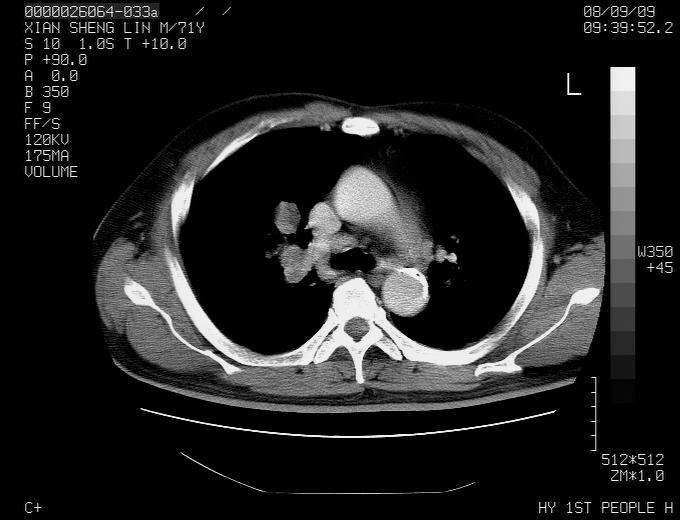

标题: CT15869:男性,71岁,因咳嗽而就诊,请讨论右上肺病变性质 [打印本页]

标题: CT15869:男性,71岁,因咳嗽而就诊,请讨论右上肺病变性质

患者,男性,71岁,因咳嗽而就诊,

典型的右肺中心性肺癌并纵隔淋巴结转移

病灶中等程度强化 还是支持肺癌诊断

考虑右肺中心性肺癌并右肺门及纵隔淋巴结转移。

1,右肺中心型ca,气管隆突旁淋巴结转移。

2,右膈明显抬高,建议肝脏扫描排除转移或原发灶。